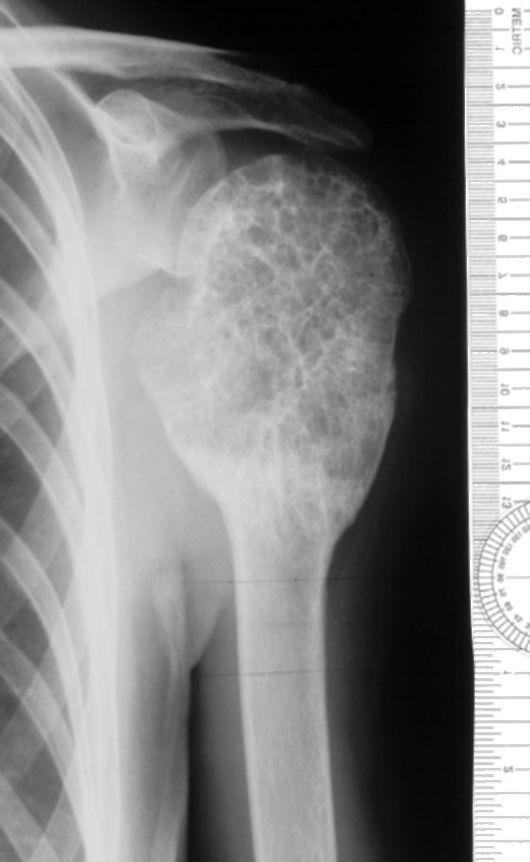

Рентгеновские снимки саркомы плечевого сустава